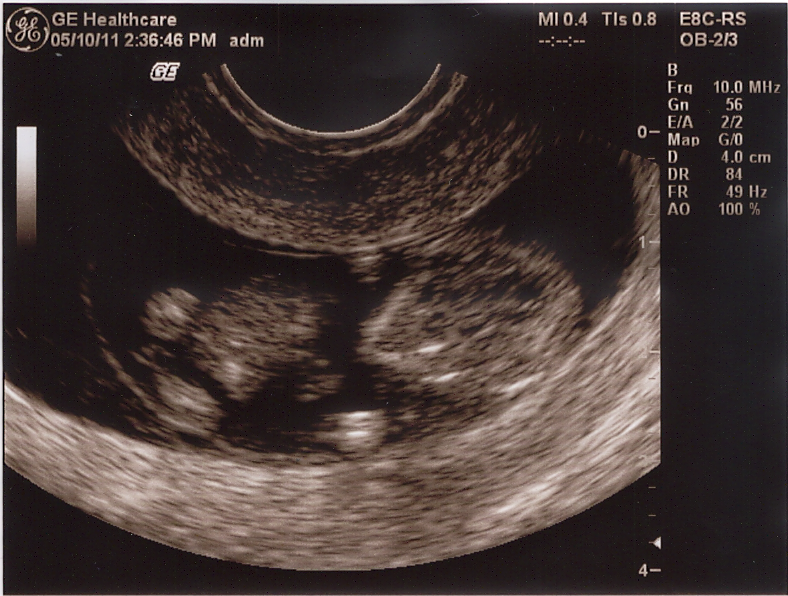

Our little newbie!